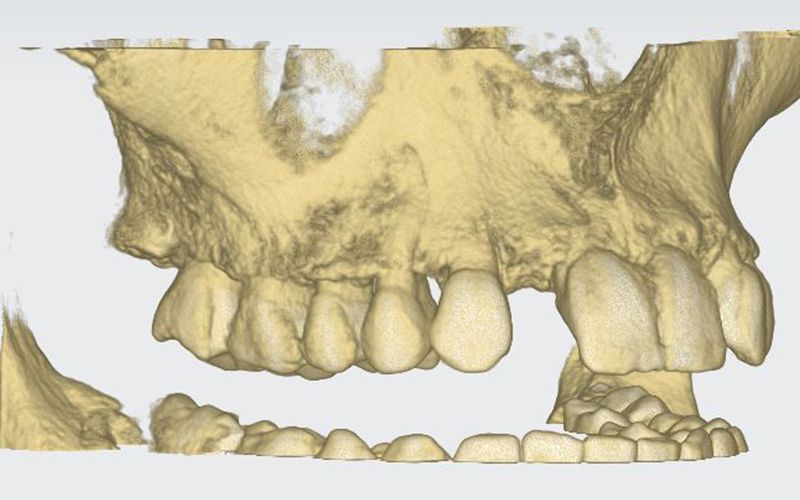

Al cabo de todo este tiempo se realizó un CBCT maxilar para iniciar la planificación de la cirugía de colocación de dos implantes en posición de 12 y 22. Durante el análisis de las imágenes radiográficas, tal y como indican las mediciones que se realizaron, se observó una limitación de espacio en sentido mesio-distal entre 11 – 13 y 21 – 23, que iba a impedir la colocación de dos implantes estándar de 3.3 mm de diámetro.

Dadas las circunstancias y para buscar una resolución óptima del caso, se decidió utilizar implantes Biomimetic Pearl de diámetro reducido de 2.8 mm de Avinent Implant System. Estos mini-implantes disponen de una línea protésica para rehabilitaciones unitarias y, dentro de su amplia gama, encontramos el que se ajustaba mejor a las exigencias del caso, permitiendo mantener perfectamente la distribución de espacio para poder respetar la biología de la rehabilitación.

Se llevó a cabo la cirugía de colocación simultanea de los implantes Pearl de 2.8 x 13 mm en posición de 12 y 22 siguiendo el protocolo indicado por la casa comercial. Estos fueron colocados con éxito a pesar de que las condiciones anatómicas no eran muy ventajosas, consiguiendo 30 Ncm de torque en ambos.